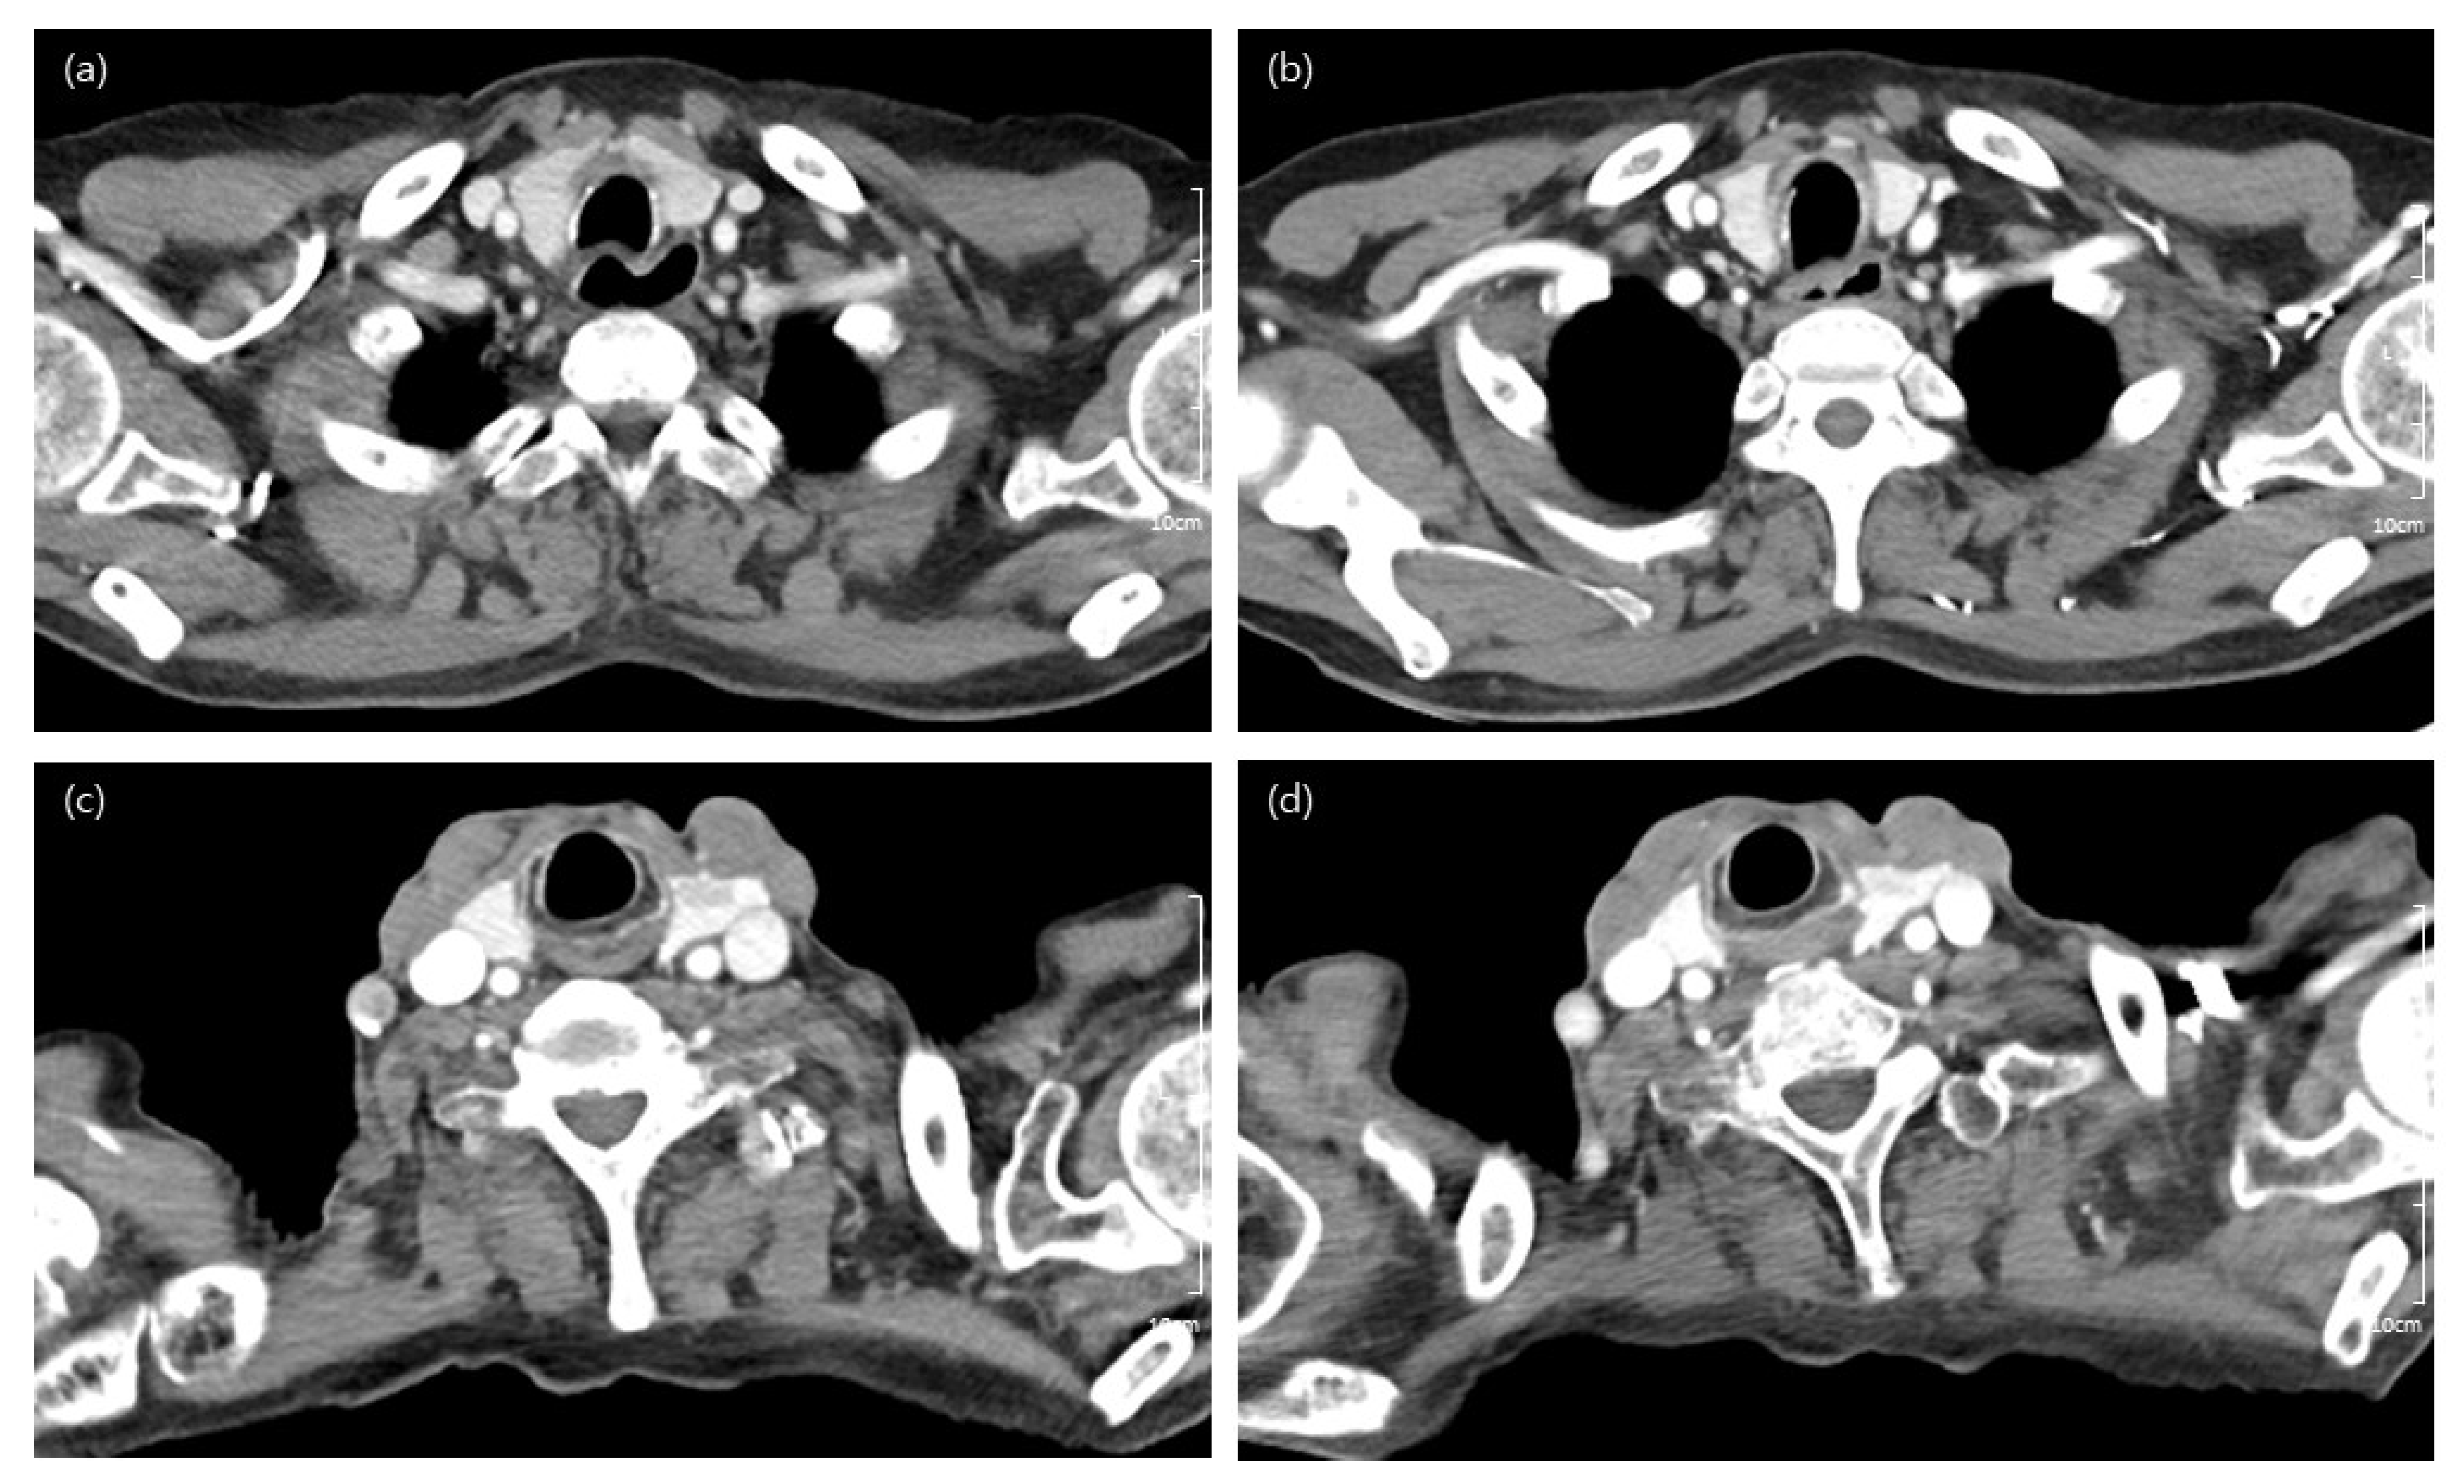

2. Material and Methods

2.2. CT Protocol